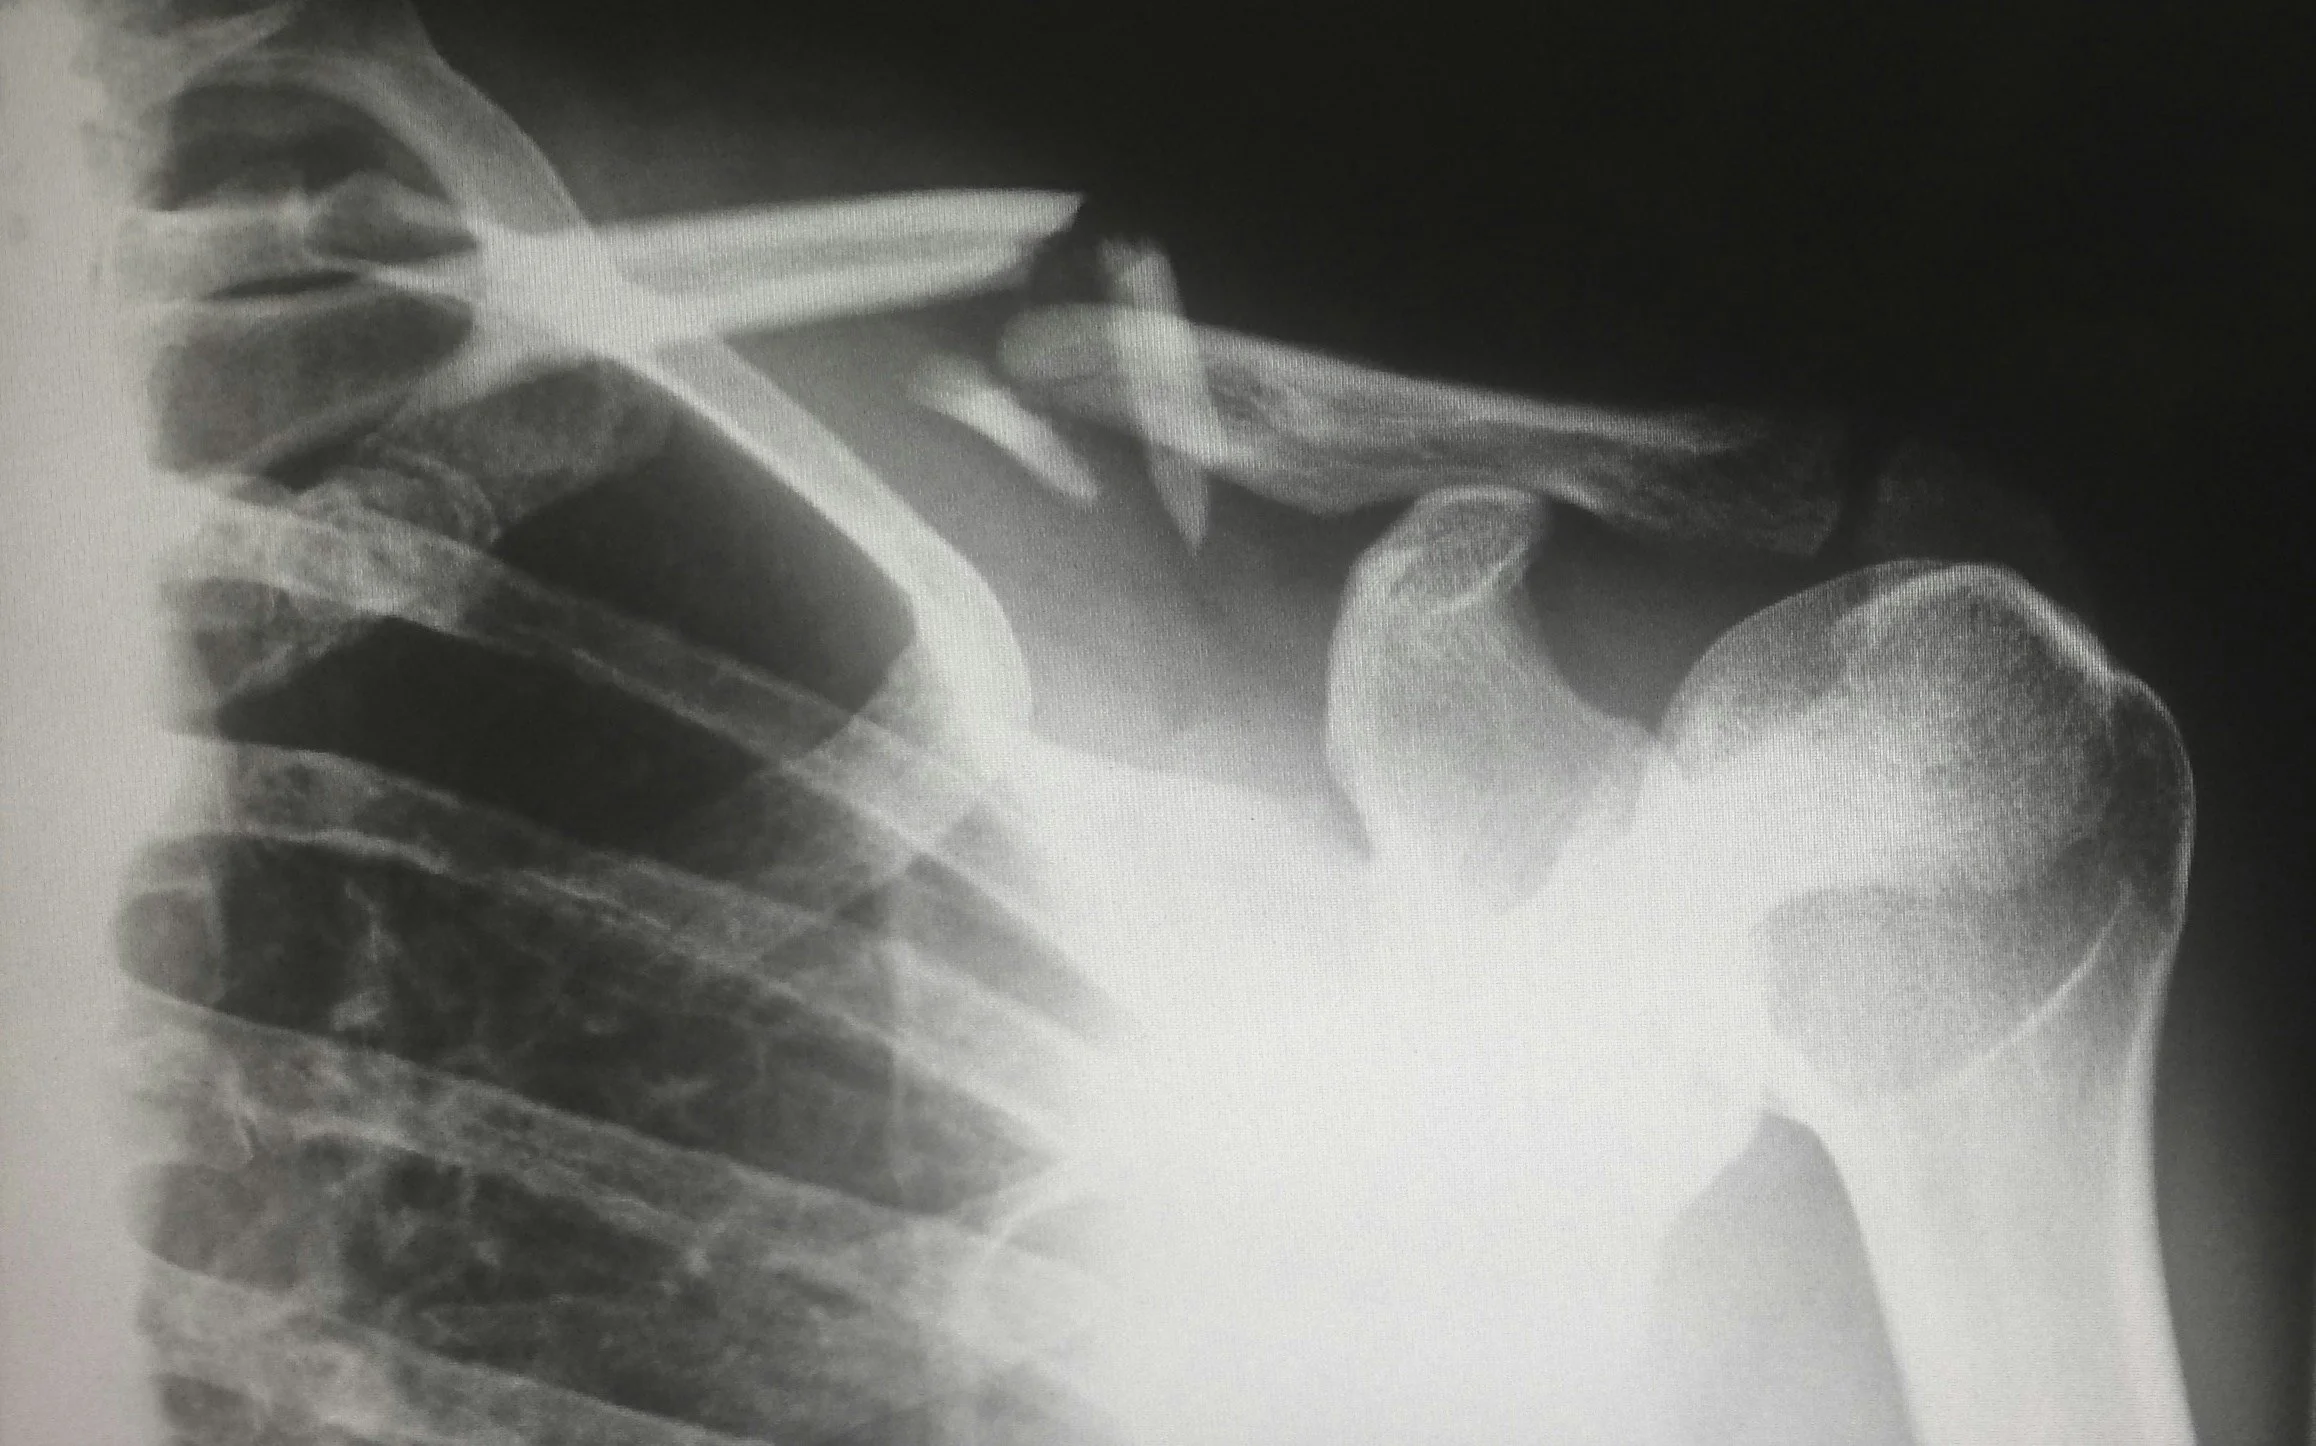

Shoulder Dystocia Maneuvers: The One Medicine Leaves Out

In the midst of a profusion of shoulder dystocia papers and publications, there is a notable absence of discussions regarding what is arguably the most effective, and least damaging, maneuver to relieve shoulder dystocia.